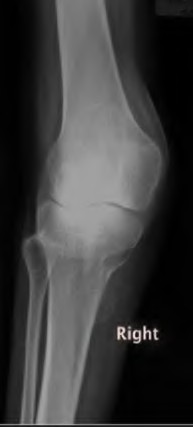

A 65-year-old woman with painful knee arthritis and the deformity seen in Figure A, is scheduled to undergo a total knee arthroplasty. All the following are risk factors for a post-operative peroneal palsy EXCEPT:

The clinical presentation is consistent with end-stage arthritis in a valgus knee. All of the factors listed are risk factors for peroneal nerve palsy EXCEPT female gender, which is not a risk factor.

Peroneal nerve palsy is a potential serious complication of TKA in patients with a pre-operative valgus knee deformity. Peroneal nerve palsy is likely caused by lengthening of the lateral aspect of the knee and subsequent traction on the peroneal nerve. It is generally recommended that patients be evaluated

carefully for symptoms postoperatively. If peroneal nerve palsy symptoms are discovered, the knee should be flexed to relax the tension that is effectively being placed on the nerve. If peri-operative nerve exploration or decompression is undertaken, the posterior border of the biceps-femoris tendon is the proper site of identification.

Idusuyi et al. published a retrospective review of 32 postoperative peroneal nerve palsies in thirty patients in which they identified possible risk factors. Prior proximal tibial osteotomy, lumbar laminectomy (thought to be a “double-crush” phenomenon), and preoperative valgus alignment of 12 degrees or more were all identified as risk factors. Other concerns included epidural anesthesia for postop pain control, preoperative flexion contractures and tourniquette time greater than 120 minutes also increased concern.

Favorito et al reviewed valgus total knee arthroplasty and reported that the most common complications of patients with a valgus deformity include: tibiofemoral instability (2% to 70%), recurrent valgus deformity (4% to 38%), postoperative motion deficits requiring manipulation (1% to 20%), wound problems (4% to 13%), patellar stress fracture or osteonecrosis (1% to 12%), patellar tracking problems (2% to 10%), and peroneal nerve palsy (3% to 4%).

Figure A demonstrates and AP radiograph of the knee showing end-stage arthritis with severe lateral compartment narrowing.